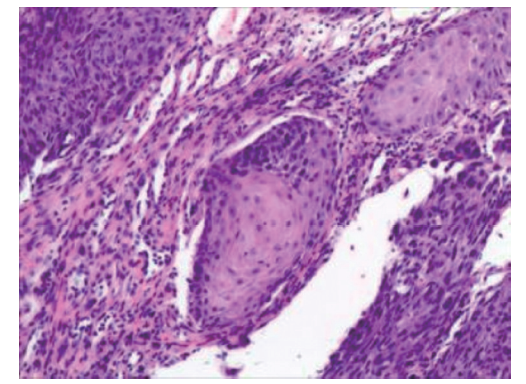

软腭及食管多原发鳞状细胞癌鼻尖皮肤转移1例

多原发鳞状细胞癌发生鼻尖皮肤转移极为罕见,文献报道较少,且鳞状细胞癌病理表现相似,较难诊断。现回顾性分析1例软腭及食管多发鳞状细胞癌出现远处鼻尖皮肤转移患者的临床资料,结合相关文献复习,以提高对本类疾病的认识。